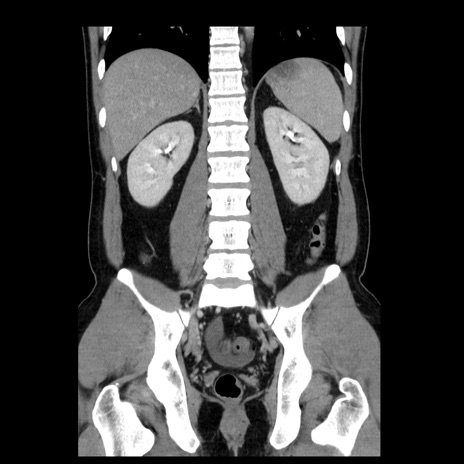

症例4(冠状断像)

【症例】30歳代男性

【主訴】腹痛、嘔吐

【現病歴】昨晩から突然の腹痛あり、その後嘔吐、軟便も出現。腹痛が改善しないため救急搬送となる。2日前にしめ鯖の食事歴あり。

【身体所見】意識清明、苦悶様、BP 135/90mmHg、BT 35.7℃、腹部:平坦、やや硬、心窩部〜臍部に自発痛、圧痛あり、筋性防御+、反跳痛-

【データ】WBC 8100、CRP 0.57